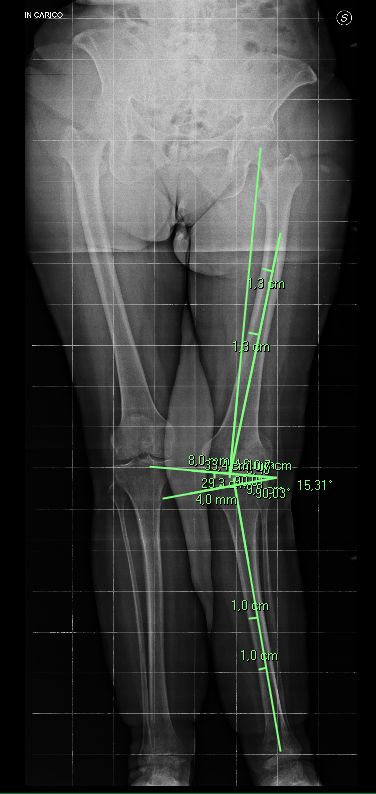

Foto e video